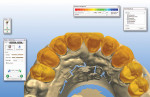

Upon completion of the custom zirconia abutments, the models were scanned and the restorations were then designed. Slight modifications were made to the temporary designs to reflect a more symmetrical proposal. These modifications were then e-mailed to the dentist for final approval before proceeding with the case (Figure 10 and Figure 11).

Fig 10 and Fig 11. A 3D proposal of the final restorations.